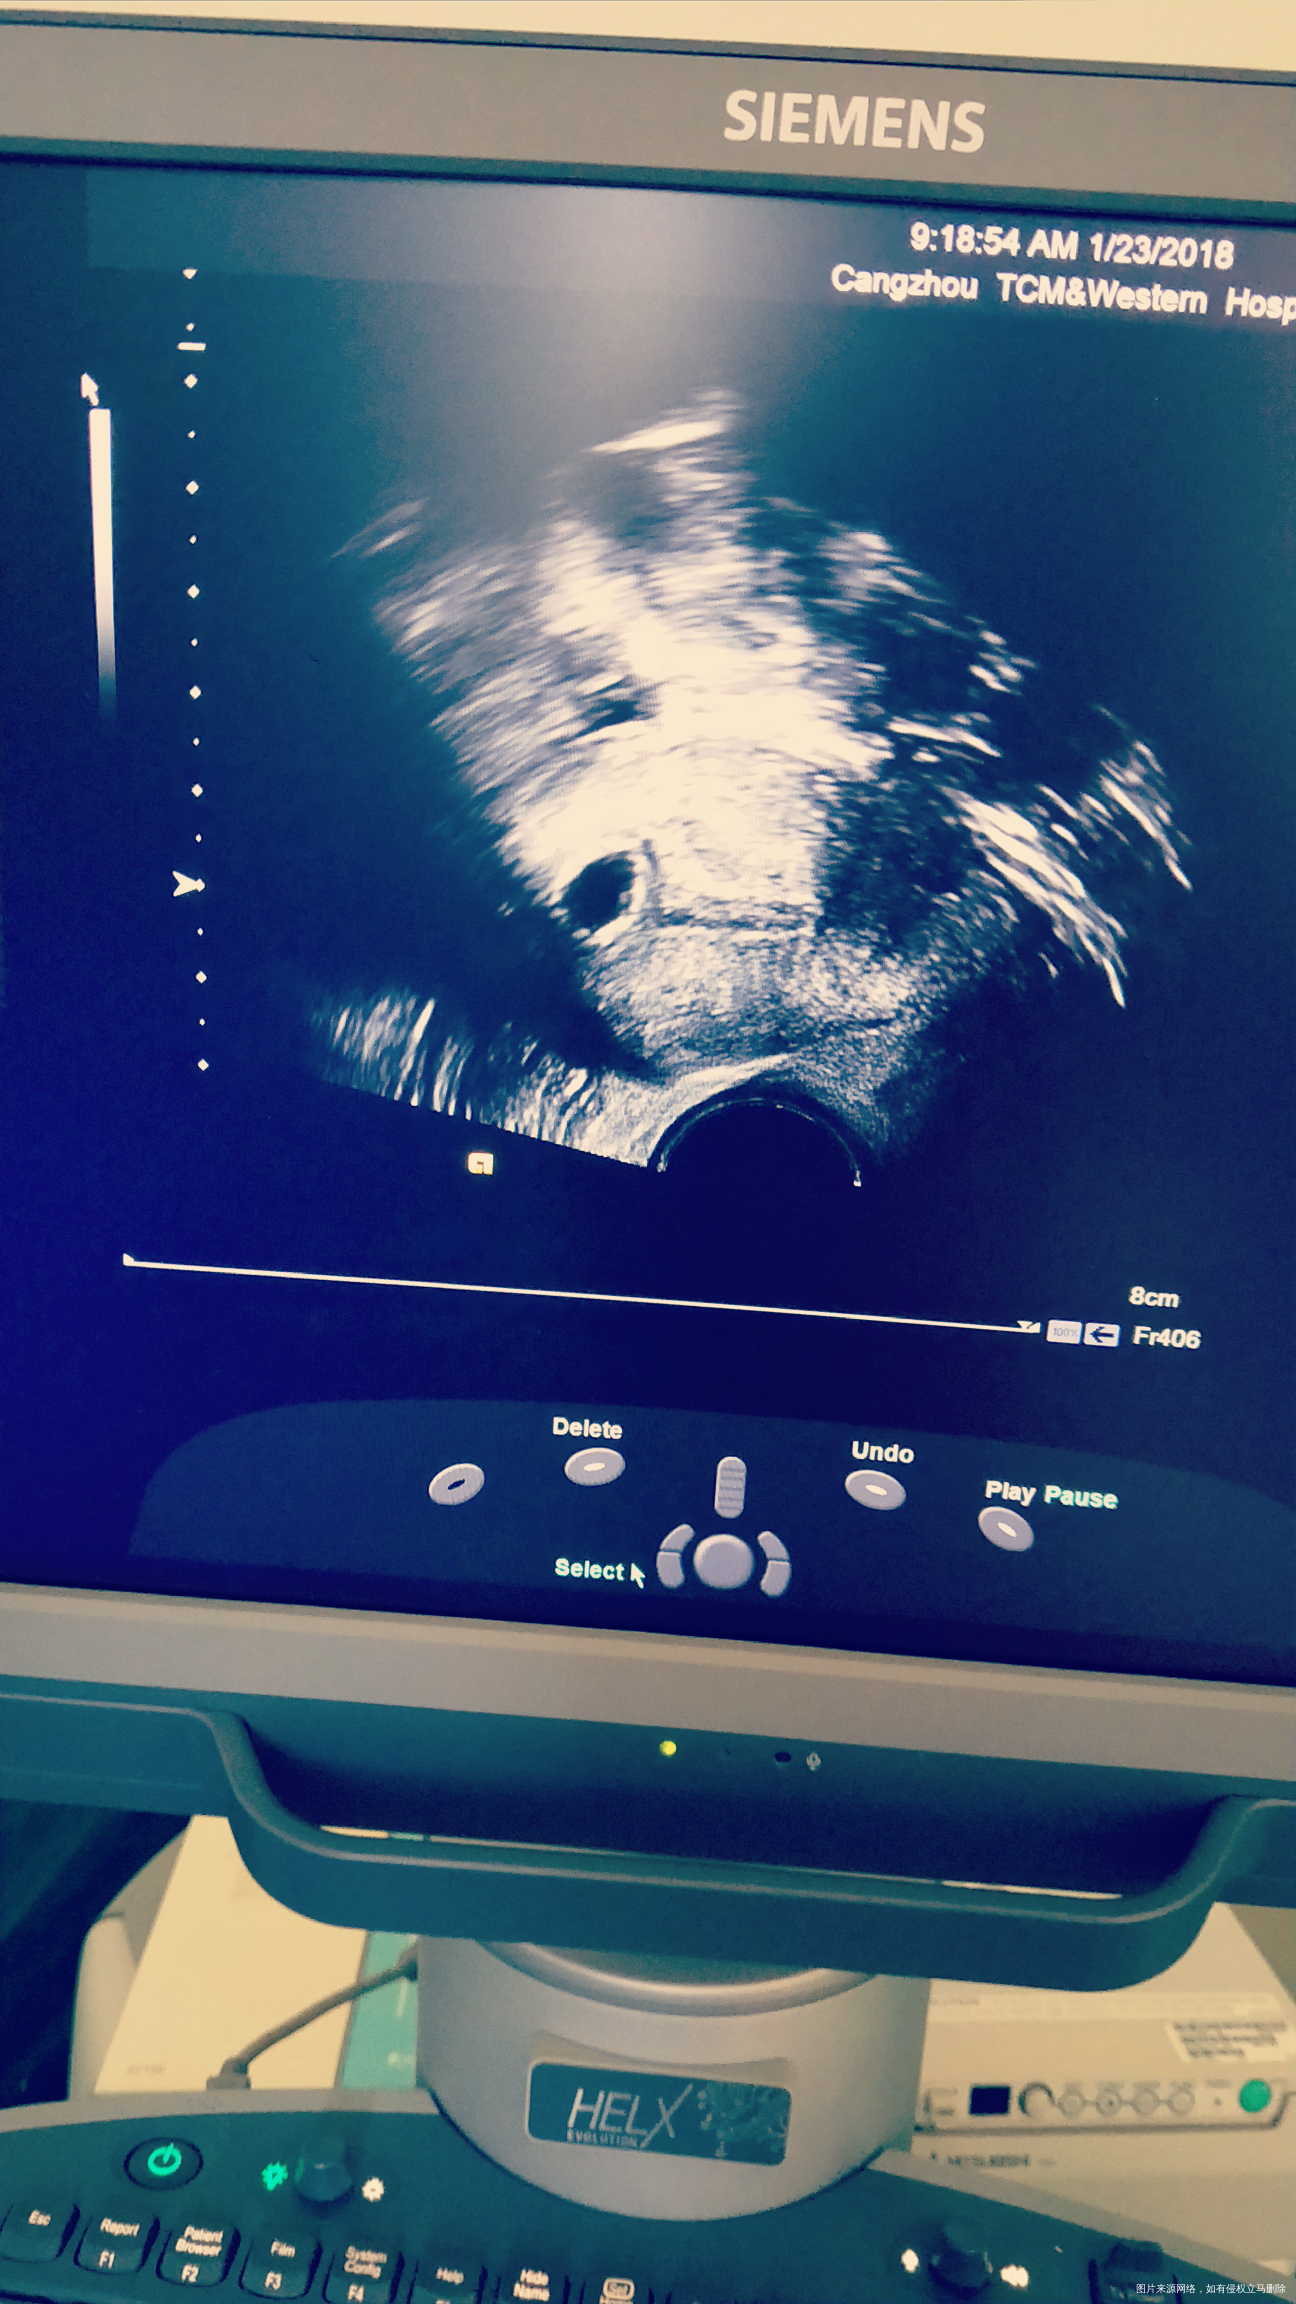

移植冻囊胚第33天做的复查,帮我看看有胎芽吗?从0.6乘0.5吃了八天的药复查才长到0.9乘0.8,一直在就褐色,今天就流血了

你好,生长缓慢,可能没有胎芽

你好啊,这个胎芽不是太明显,这个只能观察看看。

你好,看图片胎芽不是很明显

从生长速度来看应该是停止发育的可能性大。

看着好像没有胎芽,而且从生长速度来看应该是停止发育的可能性大。建议继续观察。